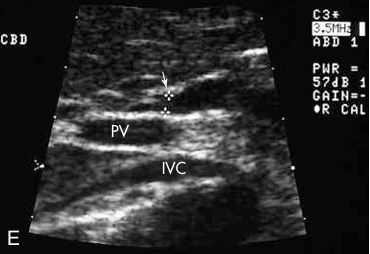

1. Portal Vein

2. Common Bile Duct

3. Gallbladder

arrow: CBD

curved arrow: CBD

Common Bile Duct doesn’t catch COLOR

SAG - CBD

On this sagittal image, the hepatic artery (HA) is shown anterior to the common duct (CD)